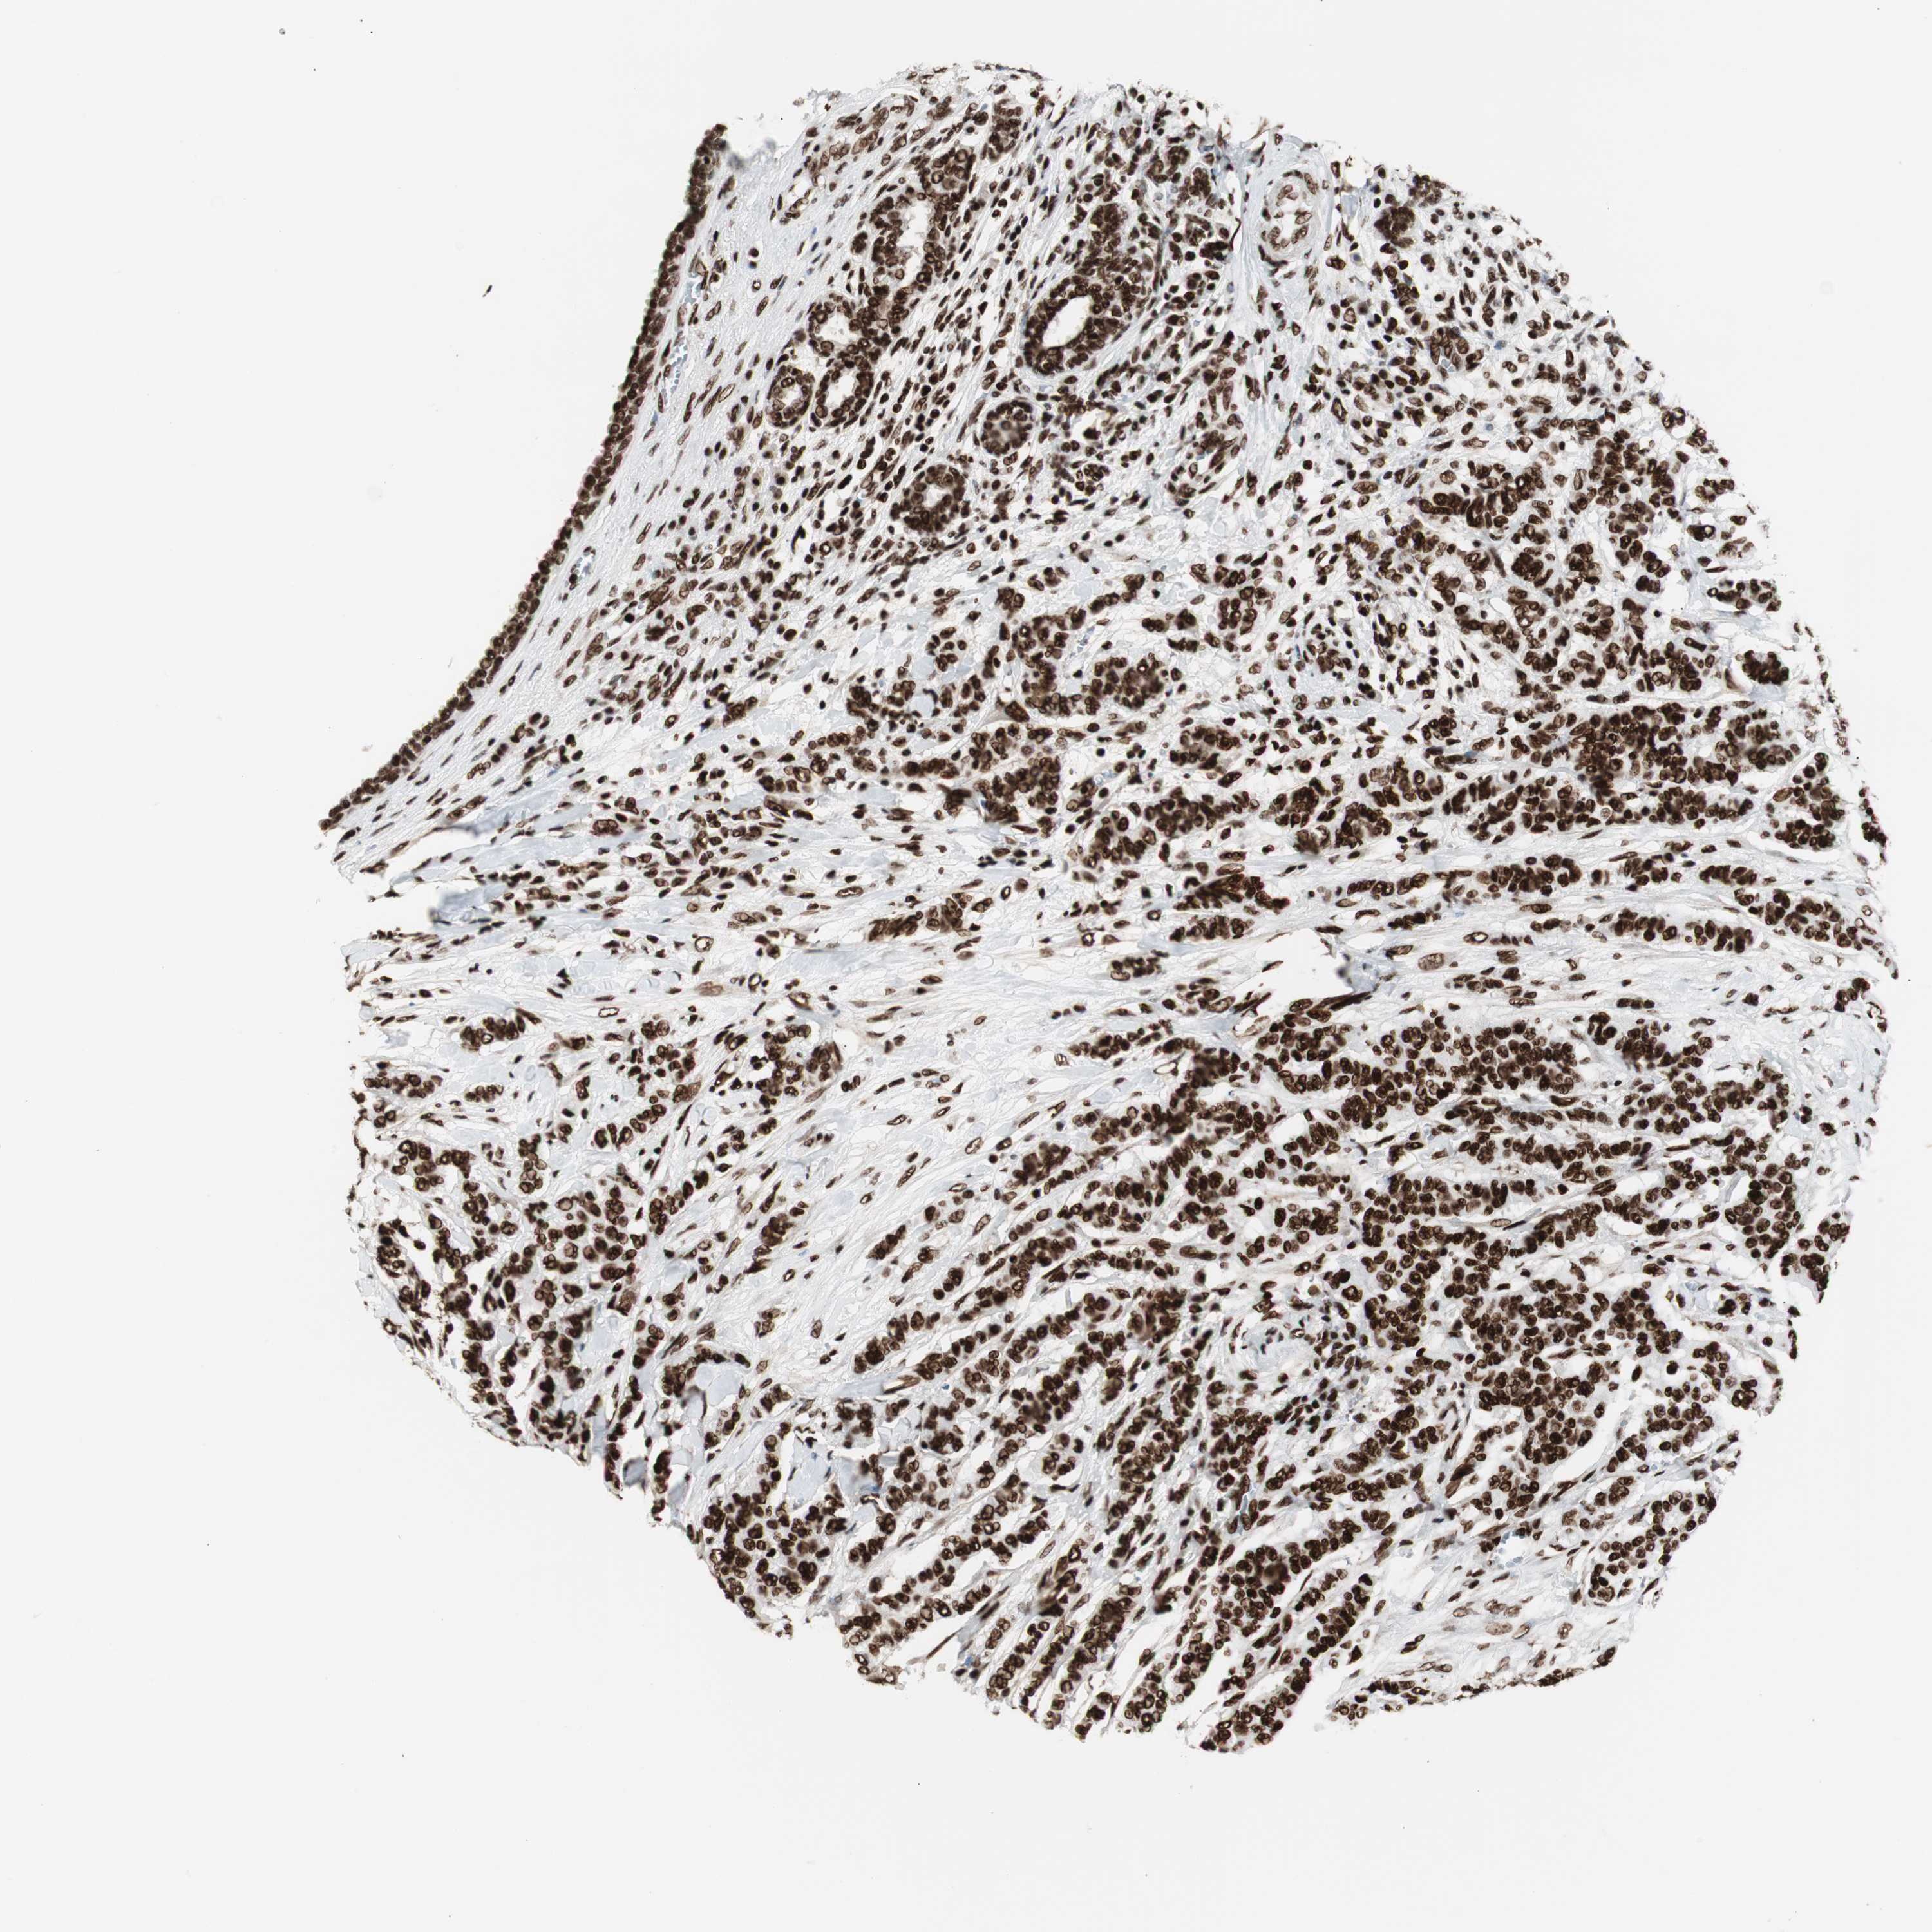

CANCER BREAST CANCER Show tissue menu

BRCA TCGA BRCA VALIDATION PROTEIN EXPRESSION

ANTIBODIES

AND

VALIDATION